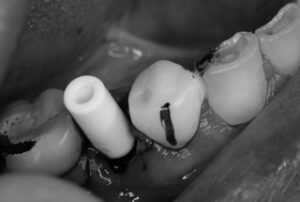

切開、抜歯から埋入、縫合までの全てを20分で終了。

その後は密着具合を示す値も良く、即日に仮歯まで装着してお帰り頂きました。